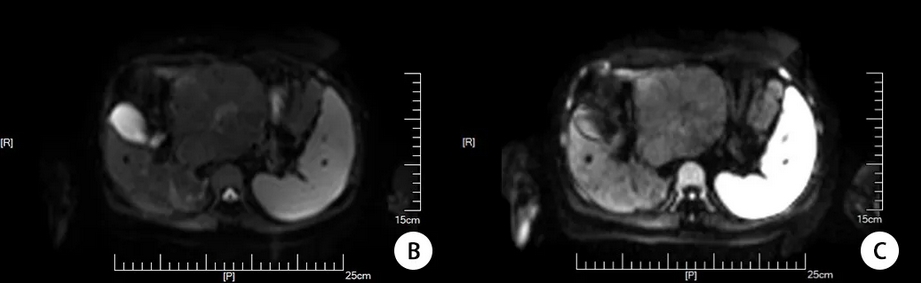

0.51U/ml,异常凝血酶原测定20.33mAU/mL,糖链抗原242 3.23IU/ml。余未见明显异常。 2023-09-04胸腹盆增强CT示:肝左叶占位,考虑FNH可能,建议结合MRI;肝右叶异常增粗静脉血管影;肝内钙化灶,肝尾状叶囊肿;脾大;少量盆腔积液;双肺多发小结节,部分GGO,建议定期随访复查;双侧腋窝稍大淋巴结,建议结合临床。 2023-09-05上腹部MRI平扫+增强+MRCP示:肝左叶占位,考虑纤维板层样肝K,伴肝内转移可能;门静脉左支癌栓形成;肝电静脉、门静脉增宽迁曲,考虑血管畸形伴局部灌注异常;肝硬化;脾大。 2023-09-07患者在全麻下行部分肝切除术,取上腹部反L切口,长约30厘米,逐层进腹,结扎离断肝圆韧带,腹腔局部网膜粘连,分离粘连后探查:腹腔无腹水,腹盆腔未见转移结节,肝脏质地正常,肝内触及多发质韧结节,界清,较大者位于左尾状叶,直径约12cm。胆囊大小如常,胆总管不增粗,肝门部未见肿大淋巴结。胃、十二指肠、胰腺、脾脏未及异常。 结合术前检查,术中诊断:肝多发FNH,拟行尾状叶切除+左肝结节活检。离断镰状韧带,左管状韧带,左三角韧带,充分游离左肝。打开肝胃韧带,结扎离断变异左肝动脉,充分显露肿块。将肿瘤掀起,显露后方下腔静脉,结扎离断数支发至腔旁尾叶的肝段静脉后,于肿瘤右侧缘紧贴肿瘤用超声刀离断肝实质,离断过程中游离数支肿瘤滋养动脉,分别结扎后离断。在离断肝实质过程中,逐步显露下腔静脉前壁至右侧尾状叶,分别显露结扎至尾状叶的肝短静脉,自下而上紧贴肿瘤至全尾状叶完整切除。另取左外叶一结节,超声刀将其完整取下,移除尾状叶及左外叶结节手术标本。蒸馏水冲洗手术野,检查术区无活动性出血、胆漏,于文氏孔及肝断面各置硅胶管一根。清点器械敷料无误,逐层关腹术毕。 手术顺利,麻醉满意,术中阻断肝门3次,每次约15min,出血约1000毫升,输血900毫升,术中取材:尾状叶肿瘤:肝脏组织一块,16cm*12cm*9cm,距肝烧灼缘3.5cm见一2*1cm的灰白纠集区;左外叶肝结节:肝脏组织一块,7cm*5cm*1cm,局部已剖开,紧邻烧灼缘见第一处结节,2cm*1.5cm*1.3cm,切面灰黄,距第一处结节2.5cm距烧灼缘1cm见第二处结节,1.5cm*1cm*0.8cm。标本家属过目后送检,患者安返病房。 一周后术后常规病理回报:(肝尾状叶,左外叶肝)符合局灶结节性增生。 图2:术后病理切片(低倍10×HE染色) 2023-09-11(术后4天)复查胸腹盆CT平扫示:肝左叶术后;肝内钙化灶;脾大;少量盆腔积液;双肺多发小结节,部分GGO,双侧腋窝稍大淋巴结,右侧胸腔积液。 患者术后恢复良好,无明显不适,2023-10-30复查肝胆胰脾B超示:肝部分切除术后,余肝脏未见明显异常,建议必要时结合增强影像学检查。门静脉流速稍高,门静脉右支及肝右静脉内径增宽,请结合临床。胆囊息肉,建议随访。脾脏轻度肿大。胰腺未见明显异常。肝内外胆管未见明显扩张。复查双侧腋窝淋巴结B超:未见明显异常肿大淋巴结。